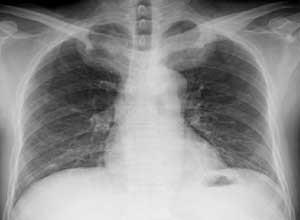

简介锁骨与第一肋骨之间的间隙较小,在解剖上是一个弱点,其中通过到上肢的神经血管束。如果锁骨或者第一肋骨在形态上有所改变就会使锁肋间隙进一步变小,而压迫基间的神经血管束产生症状,叫肋锁综合征。颈肋综合征是胸廓出口区重要的血管神经受压引起的复杂的临床症候群,又名颈胸廓出口综合征(thoracic outlet syndrome,TOS)、前斜角肌综合征、胸小肌综合征、肋锁综合征、过度外展综合征等,是指胸廓上口出口处,由于某种原因导致臂丛神经、锁骨下动静脉受压迫而产生的一系列上肢血管、神经症状的总称。